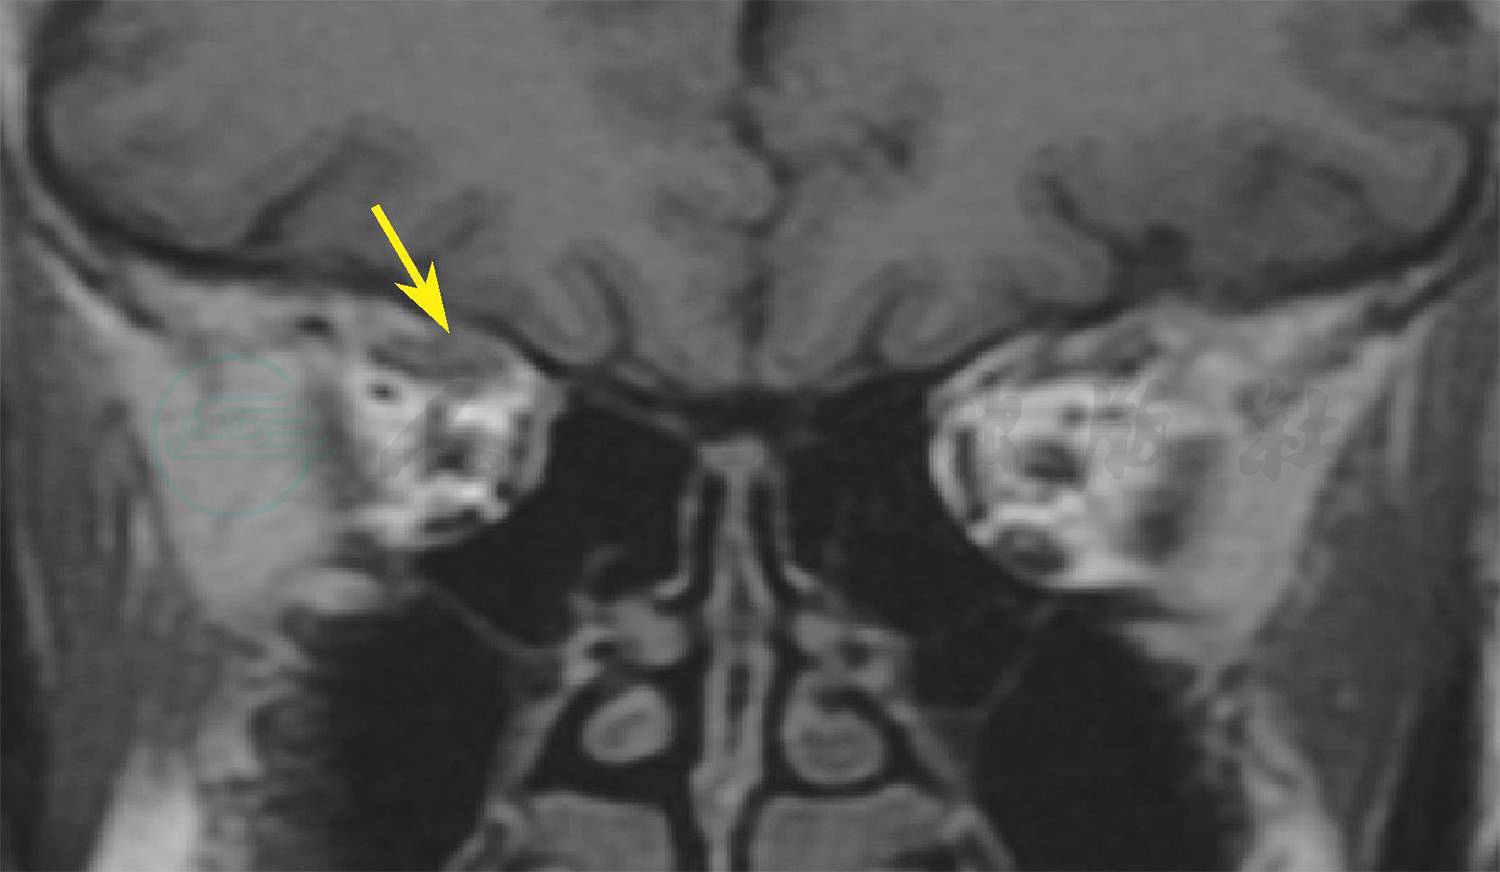

分析患者病情:患者复视发生于白内障术后一周,此后逐渐加重,术中麻醉方式为表面麻醉联合球后麻醉。于是先行眼眶CT排查是否存在不自知的外伤引起的眼眶骨折。眼眶CT示:近总腱环处上直肌增粗,周围脂肪间隙边界模糊,眶骨连续性完整;随后行眼眶核磁共振检查,核磁影像显示:近总腱环处上直肌肌腹增粗(图2,图3)。考虑到手术前无斜视,手术中局麻采用球后注射,术后早期出现复视,随时间延长斜视逐渐加重,并结合典型近总腱环周围肌肉增粗的影像学表现,诊断为麻醉相关性斜视。

图2 眼眶核磁

黄箭头所示位置为上直肌近总腱环处肌腹增厚。